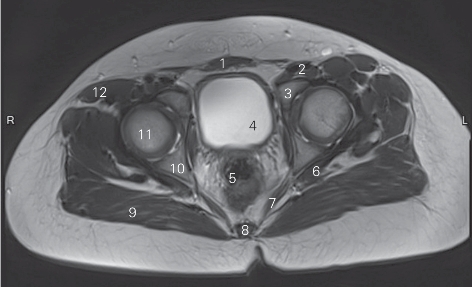

图5-4 经股骨头的横断层MR T1加权图像

1 腹直肌 rectus abdominis 2 股动、静脉 femoral artery and vein

3 耻骨体 body of pubic 4 膀胱 urinary bladder

5 直肠 rectum 6 上孖肌 gemellus superior

7 肛提肌 levator ani 8 尾骨 coccyx

9 臀大肌 gluteus maximus 10 坐骨体 body of ischium

11 股骨头 head of femur 12 阔筋膜张肌 tensor fasciae latae